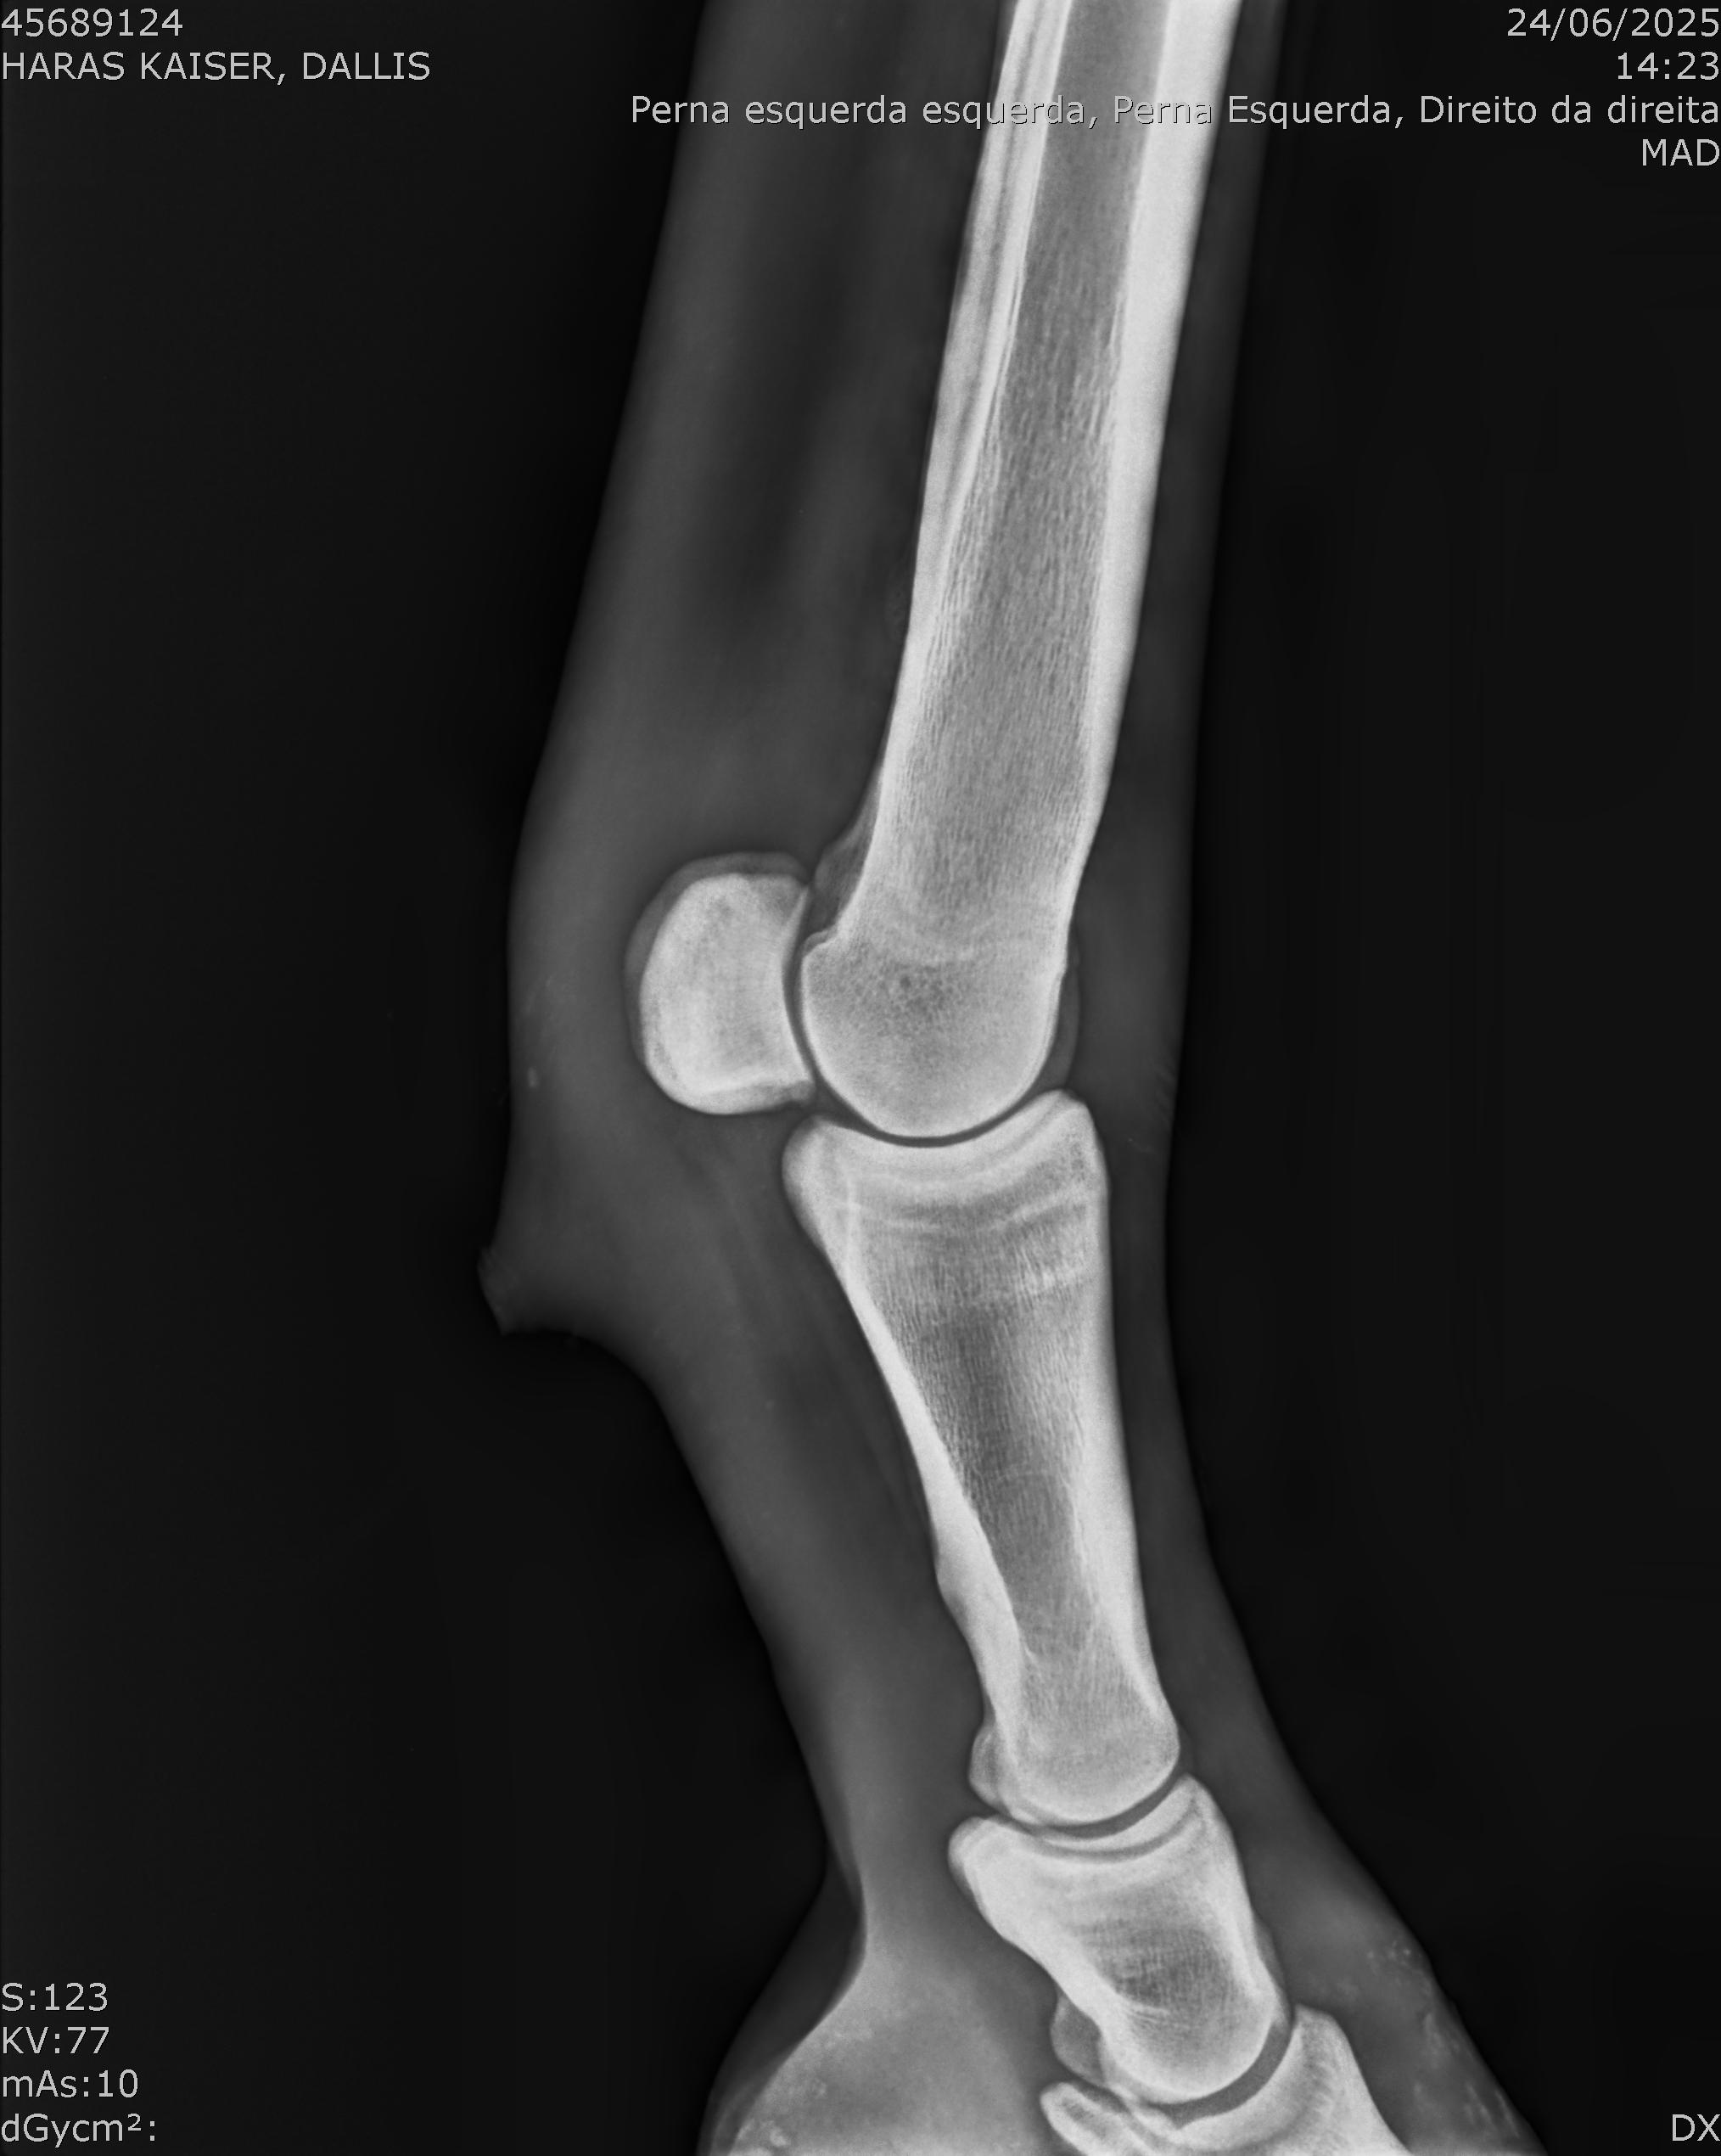

:: RAIOS-X DO LOTE